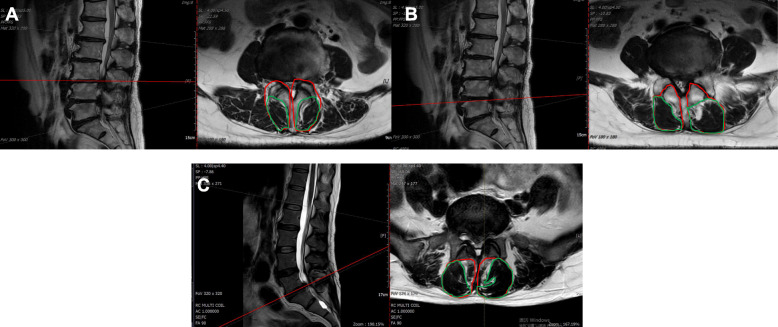

Fig. 1.

Measurements of TCSA and TFCSA at the L3/L4 (A), L4/L5 (B), and L5/S1(C) intervertebral discs. Red margins outline the multifidus muscle cross-sectional area (TCSA), while green margins outline the fat-free multifidus muscle cross-sectional area (TFSCA)